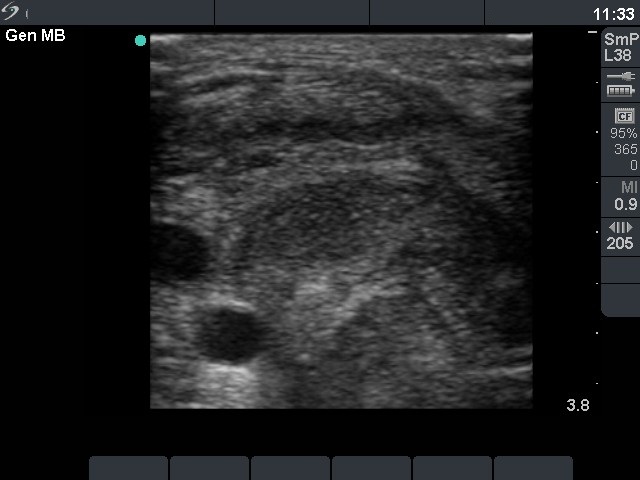

Follow-up investigations (6-8. rows of images):

Six weeks after the two sessions of therapy the nodule presented a dramatic decrease in size and decreased further in the next two years.